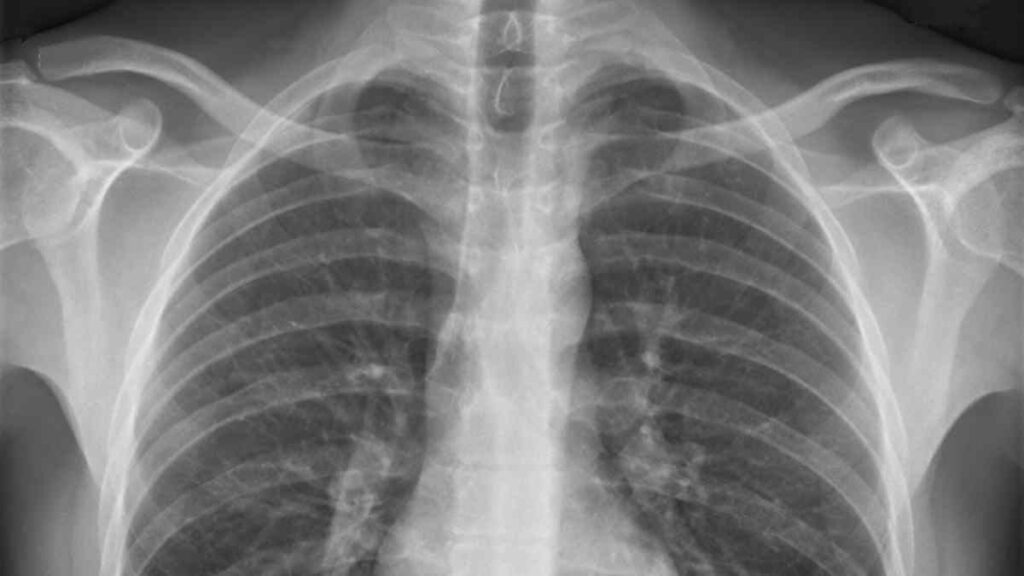

The central argument of the federation is the exposure to dust free of Respirable Crystalline Silica (RCS) that is generated in these activities. The union recalls that SCR is officially categorized as a carcinogenic agent according to Royal Decree 665/1997.

Continued exposure to this agent can cause silicosis and lung cancer, both pathologies recognized as ‘Occupational Diseases’ by the Spanish health system. UGT FICA hopes that the General Directorate of Social Security Management will consider the request and begin the feasibility analysis.